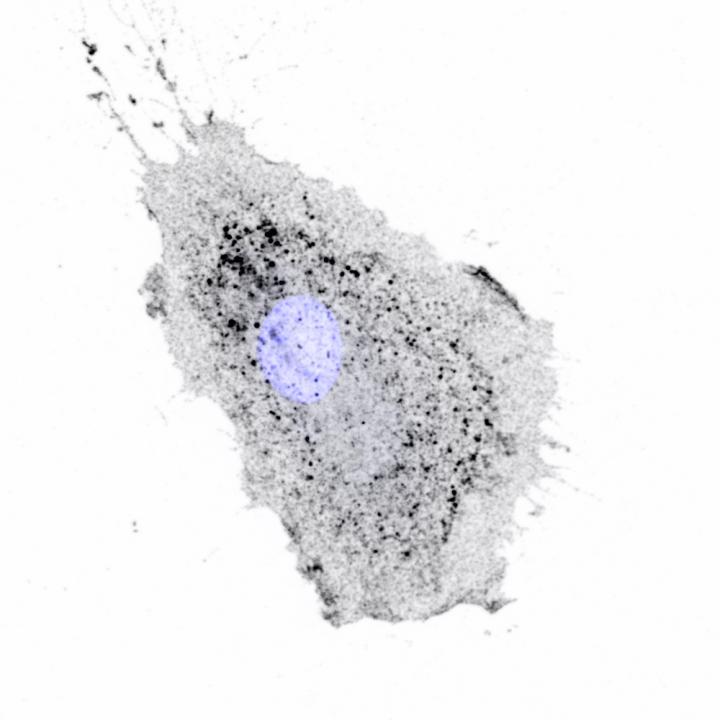

image: Integrins being moved inside a migrating cell. Integrins appear as dark spots, cell nucleus is blue.

The researchers are investigating a tiny cell component called an Intracellular nanovesicle (INV) which acts like a courier within a cell by transporting cargo to where it is needed. When a cell moves, the INV moves a particle called an integrin from the cell's surface to 'unstick it' from the surface it is attached to. It then recycles and replaces the integrin to stick it to a new surface.

To investigate TPD54's role in cell movement, the Warwick team observed cells migrating on a surface coated with fibronectin, a type of extra-cellular matrix, using a live cell microscope. They then reduced or increased the expression of the protein TPD54 to mimic the expression in a cancer cell, observing how the cell migrates more or less depending upon the levels of TPD54.

The Warwick group discovered INVs in 2019, having previously been overlooked. At around 30 nanometres across, they were so small that the team had to use a combination of electron microscopy and the Warwick Open Source Microscope, a super-resolution light microscope built at the University of Warwick, to observe them.